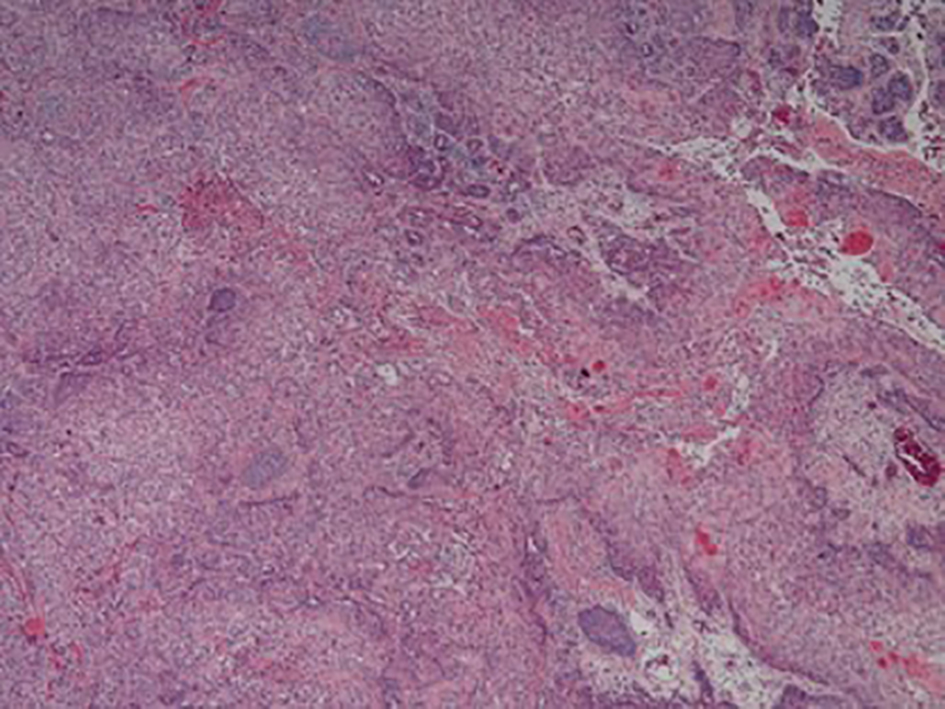

The specimen was analyzed using direct microscopy, hematoxylin and eosin (H&E) stain, and chromogenic in situ hybridization (CISH). The specimen was positive for partially keratinized ulcerative SCC of the scalp that was moderately differentiated and invasive, as seen in Figure 1. The tumor cells were described as large with irregular, atypical, hyperchromatic nuclei with nucleoli, which can be observed in Figure 2.

![]() Click for large image | Figure 1. Low magnification. Invasive partially keratinized squamous cell carcinoma. |